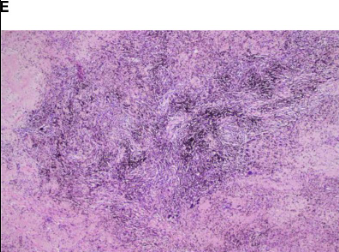

术后病理

术后病理证实为ypT0N0M0,13枚清扫淋巴结(5-7组、10-12组)均无肿瘤累及;镜下未见残留肺腺癌细胞,仅见局灶凝固性坏死、纤维组织增生及淋巴细胞浸润。